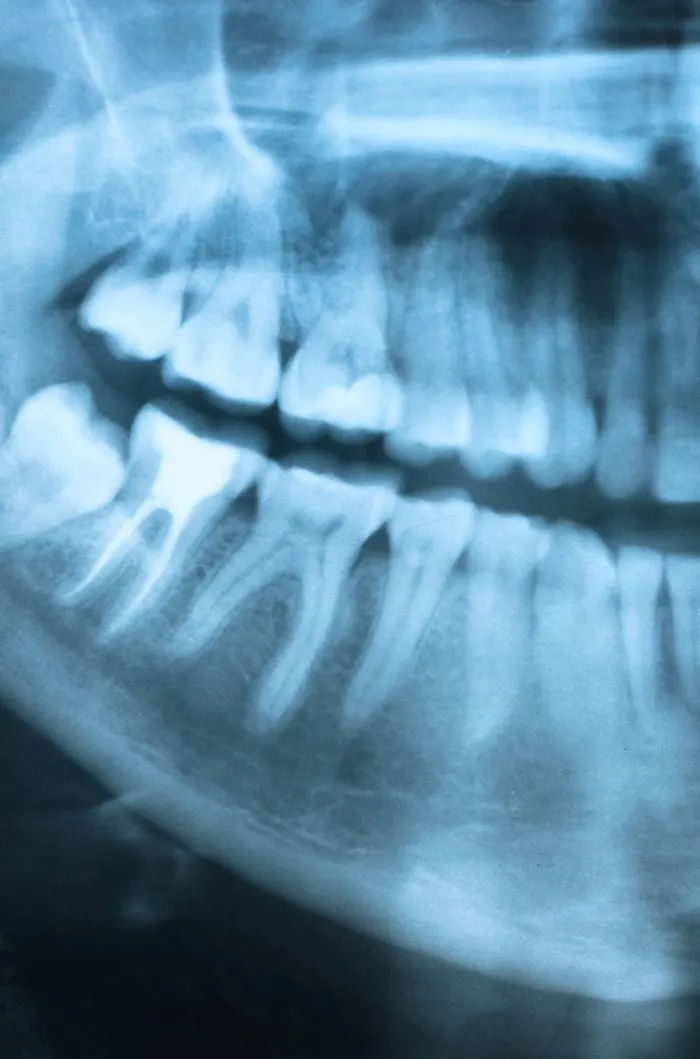

Digital X-Rays & Imaging

Better diagnostics means better results. With modern imaging techniques, we can quickly and accurately assess your dental emergency, and create a treatment plan right away, so you can relieve your dental pain and get back to your life.